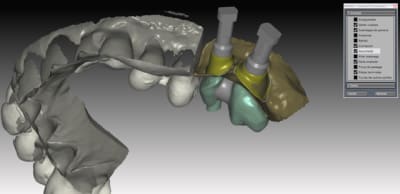

donc voici comme promis piliers ZR sur base Titan

passivité total de l'armature , les piliers sont tous réglés , parallélisés lors de la modélisation de l'ensemble . l'usinage des piliers et de l'armature ce fait séparement pour encore qualité d'ajustage..

Dans le ce cas present Strauman BL 3.3 rc

collage des base titan avec du multilink automix

ce cas est en cour de réalisation , essayage de l'ensemble

déja validé ... je n ai pas de eu de photos , aucun blanchiment de gencive , merci l'ajustage des profils d'émergence dans le soft qui est vraiment bien fait ..

*

a suivre..

je m'éclate vraiment avec les possibilitées qu'offrent le system d'usinage ...

Pour l'instant 100% de client satisfait pourvu que ca dure....